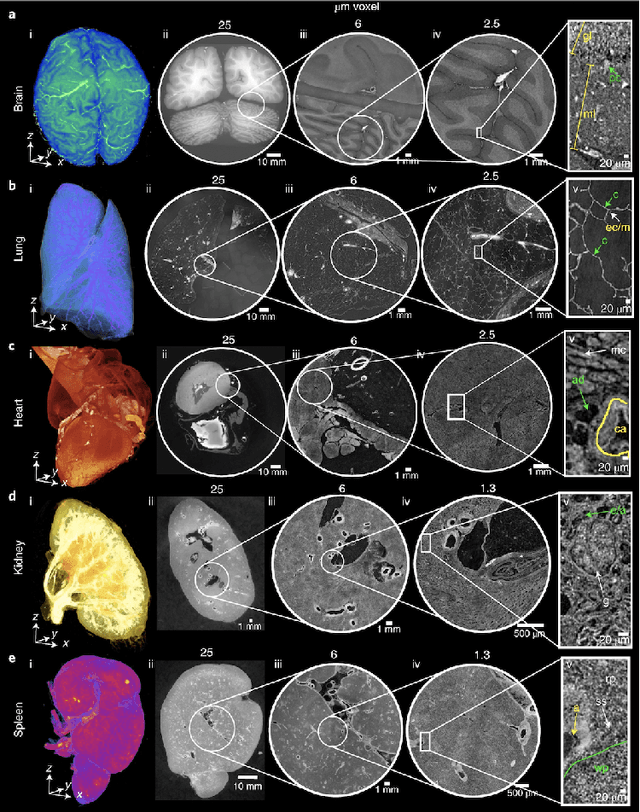

Abstract:Automated blood vessel segmentation is vital for biomedical imaging, as vessel changes indicate many pathologies. Still, precise segmentation is difficult due to the complexity of vascular structures, anatomical variations across patients, the scarcity of annotated public datasets, and the quality of images. We present a thorough literature review, highlighting the state of machine learning techniques across diverse organs. Our goal is to provide a foundation on the topic and identify a robust baseline model for application to vascular segmentation in a new imaging modality, Hierarchical Phase Contrast Tomography (HiP CT). Introduced in 2020 at the European Synchrotron Radiation Facility, HiP CT enables 3D imaging of complete organs at an unprecedented resolution of ca. 20mm per voxel, with the capability for localized zooms in selected regions down to 1mm per voxel without sectioning. We have created a training dataset with double annotator validated vascular data from three kidneys imaged with HiP CT in the context of the Human Organ Atlas Project. Finally, utilising the nnU Net model, we conduct experiments to assess the models performance on both familiar and unseen samples, employing vessel specific metrics. Our results show that while segmentations yielded reasonably high scores such as clDice values ranging from 0.82 to 0.88, certain errors persisted. Large vessels that collapsed due to the lack of hydrostatic pressure (HiP CT is an ex vivo technique) were segmented poorly. Moreover, decreased connectivity in finer vessels and higher segmentation errors at vessel boundaries were observed. Such errors obstruct the understanding of the structures by interrupting vascular tree connectivity. Through our review and outputs, we aim to set a benchmark for subsequent model evaluations using various modalities, especially with the HiP CT imaging database.